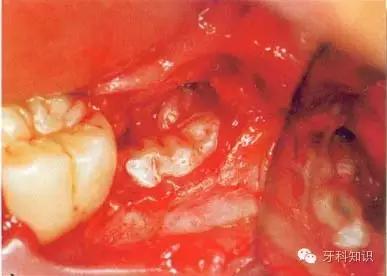

e分牙已基本完成,远中牙片挺松后即可顺利取出

f 远中牙片取出后即可拔除近中部分。术后应注意牙槽嵴顶的高度。保留颊侧骨板很重要,它有利于牙槽窝和第二磨牙牙槽骨的完全重建

g 将皮瓣复位后,磨牙后区缝合2针,此处使用的是不可吸收的聚硅酮丝线(4—0)。第一、二磨牙之间缝合1针,以维持楔状隙内龈乳头的位置并确保迅速的愈合。轻压组织至少2 min,使骨膜和骨皮质、牙龈和牙骨质粘连复位。作用于软组织的压力还能排出气泡形成良好的血凝块

h只要有根分叉且近中倾斜程度不大、车针能够顺利进入,沿牙体长轴进行的正中切割就能顺利进行。该牙的根间孔尚未完全闭合